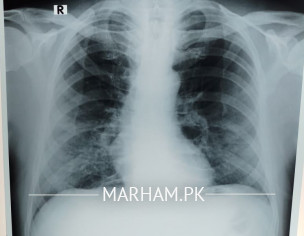

Shortness of breath no I don’t know for sure although when he speaks he starts panting and coughing after a few sentences. He’s diabetic and hypertensive both with arthritis. This is today’s xray

Can anyone pls explain what the X-ray shows? He started antibiotic on Saturday. Azomax 500 once daily with Panadol x 2 thrice a day